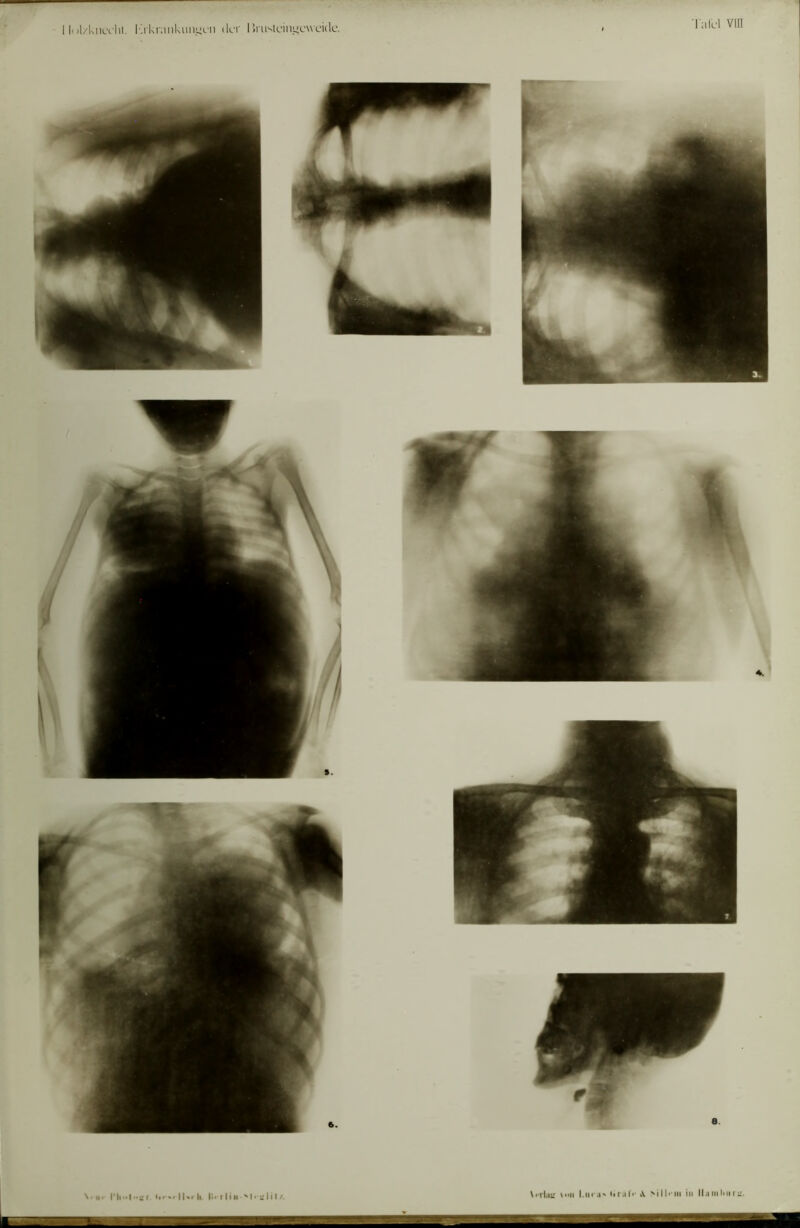

Die röntgenologische Diagnostik der Erkrankungen der Brusteingeweide : mit 60 Abbildungen im Text und 50 Röntgenbildern auf 8 Tafeln.

- Guido Holzknecht

- 1901